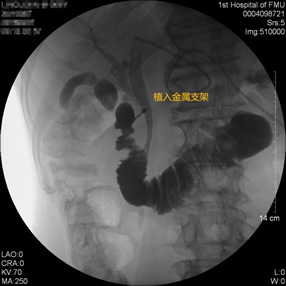

胃毕-Ⅱ术后乳头倒置 胃毕-Ⅱ术后胰管胆管双支架植入 胃毕-Ⅱ术后金属支架植入

胃毕-Ⅱ术后肝门部胆管狭窄 胃毕-Ⅱ术后金属支架植入